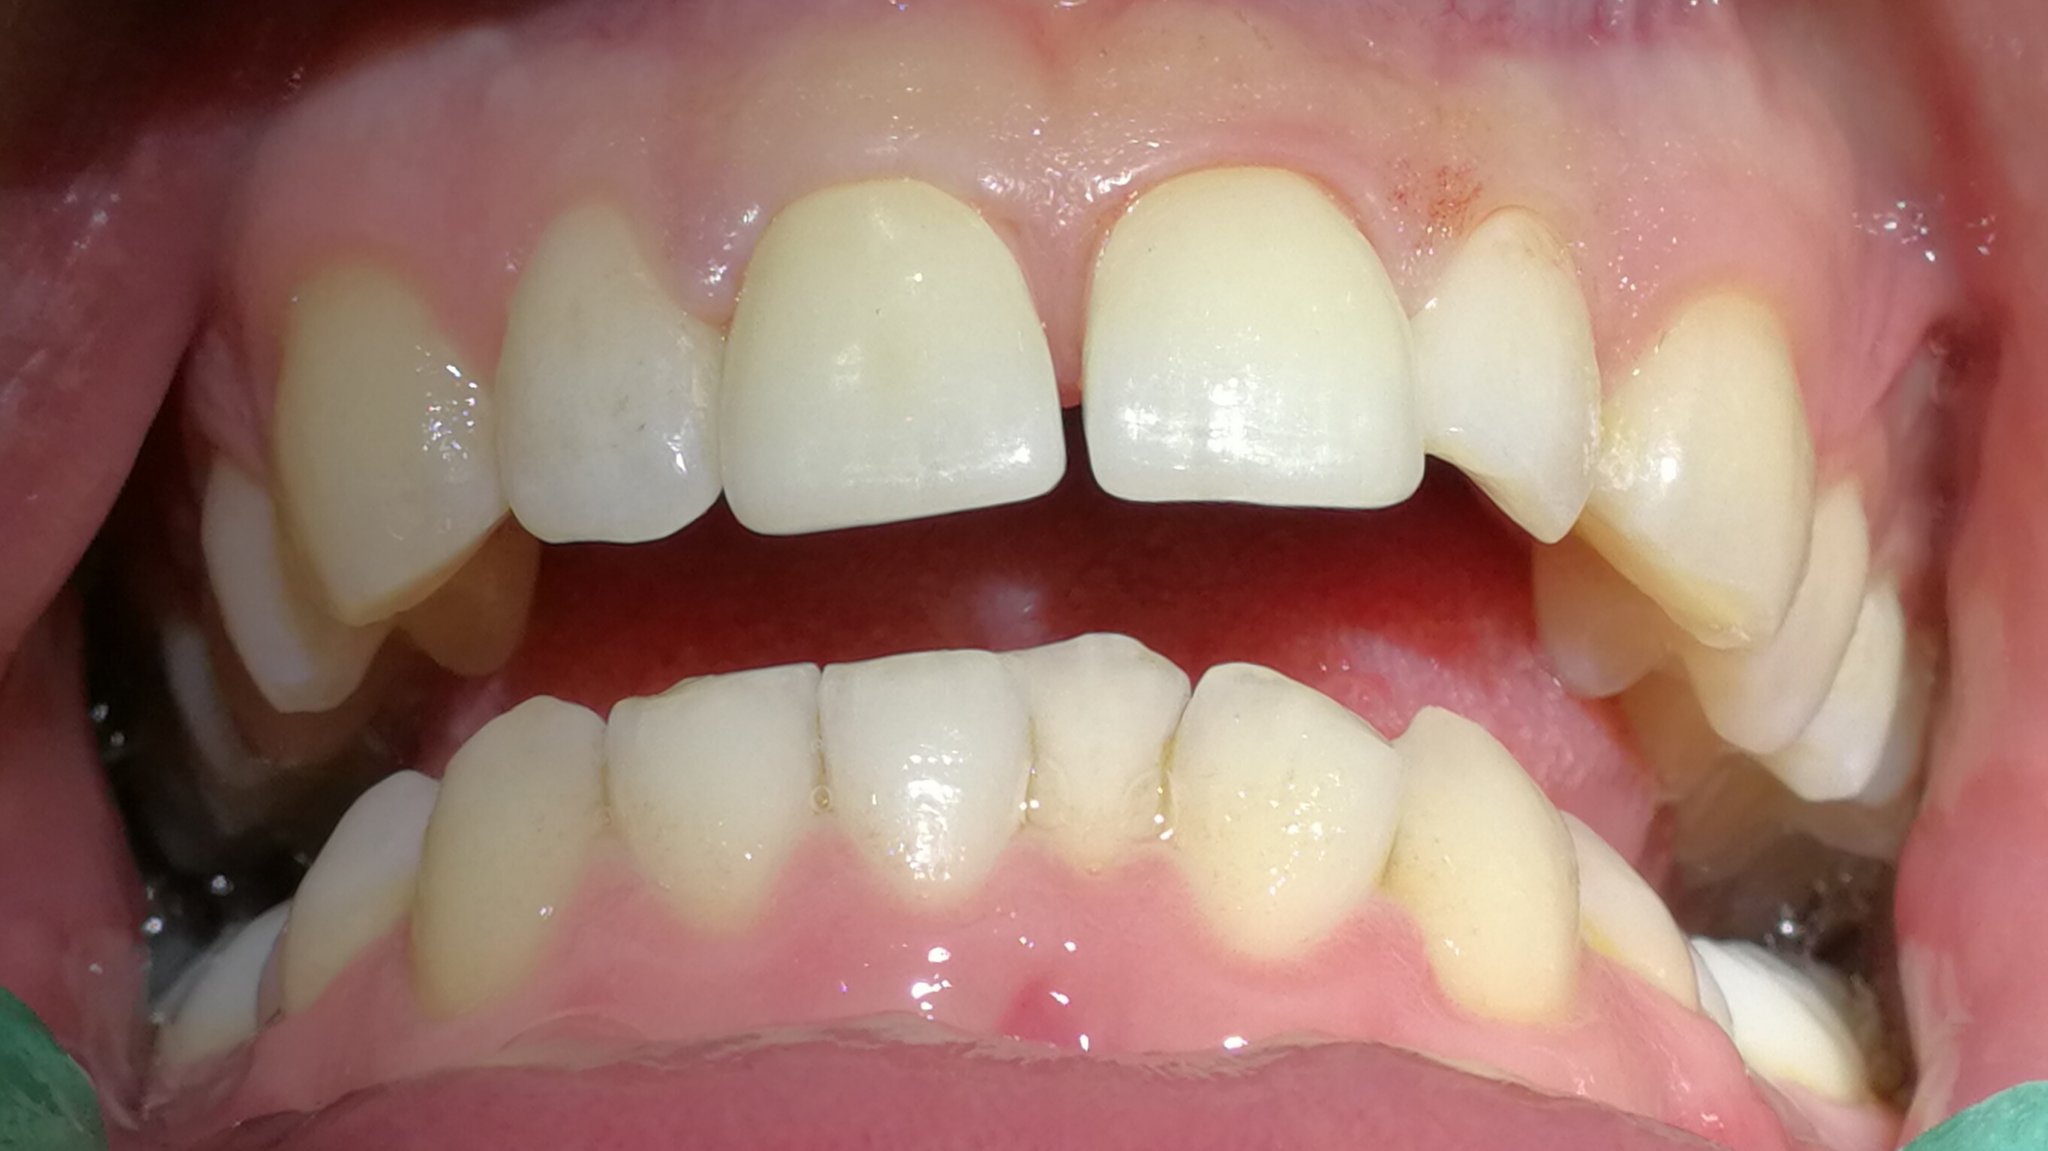

Karies und traumatische Einwirkungen (Zähneknirschen, aus Versehen auf harten Gegenstand beissen und andere Unfälle) können die Zahnhartsubstanz zerstören. Die Reparatur erfolgt in der modernen Zahnmedizin metallfrei, zahnfarben und je nach Grösse des Defektes mit den folgenden Therapiemitteln: